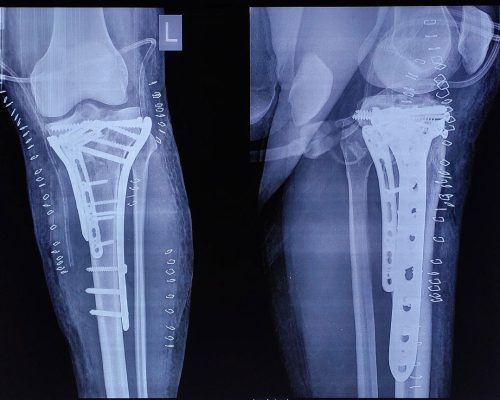

Complex Trauma Injury

Trauma (Fracture) is most common and basic orthopaedic problem. Advance Orthopedic hospital is specialized in trauma fractures from multiple options available for reconstruction like; Plate and screws (Locking, Non-locking), Intramedullary nail(Rods), K-wires. All the fracture surgery requires precision to allow early and anatomical healing and to prevent any future deformity or complications.